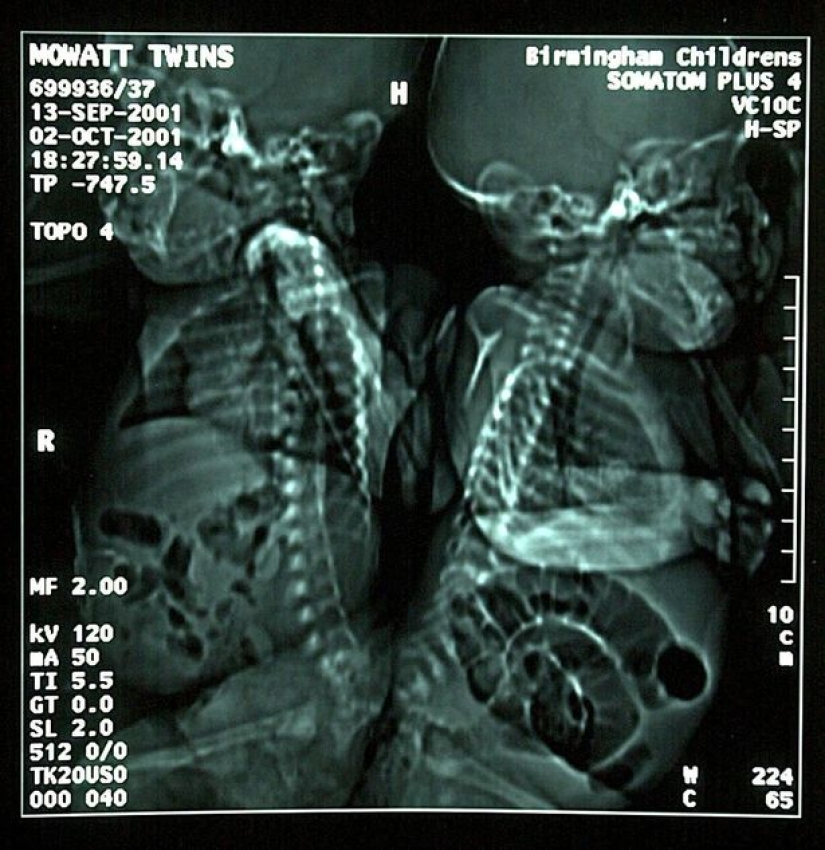

Eman and Sanchia Movatt were born on September 13, 2013, four months ahead of schedule, and even fused with spines. The fact that the doctors managed to save them at birth is a real miracle. Another thing happened when the girls were 3 months old – surgeons managed to separate the Siamese twins, saving both their lives.

At the time of surgery, the babies weighed together a little more than 4 kg. The operation lasted 16 hours and it became the second such successful surgical intervention in the history of medicine. The chances of survival of the sisters were estimated by different experts from 5 to 25 percent, but everything went perfectly.

Despite the fact that once in 2001, doctors created a miracle, they failed to fully preserve the functions of separated twins. Each of the girls has a serious defect of the spine, and in addition, each of them has one side developed a little worse and one leg is shorter. Therefore, the twins walk on crutches, and Eman sometimes uses a wheelchair.